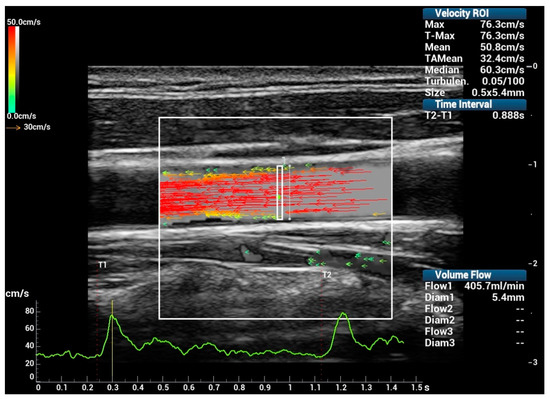

:1. Introduction

2.1. V Flow Technique Description

2.2. Ultrasound Scan Setup